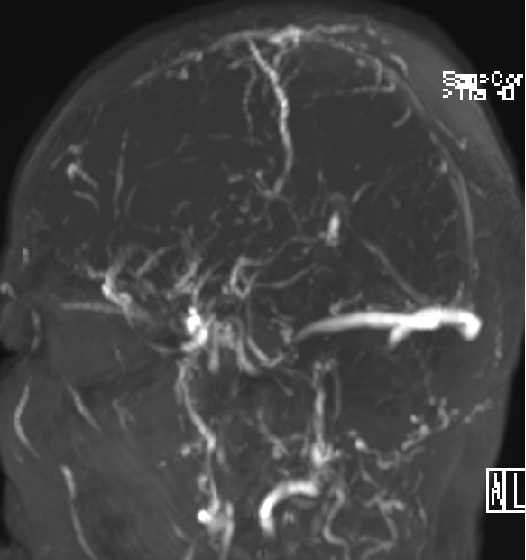

2015-1-30 DSA